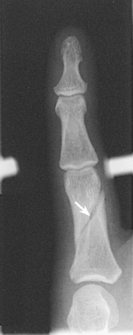

The interphalangeal (IP) articulations between the phalanges are synovial hinge type and allow only flexion and extension (Fig. 4-8). The IP joints are named by location and are differentiated as either proximal interphalangeal (PIP) or distal interphalangeal (DIP), by the digit number, and by right or left hand (e.g., the PIP articulation of the fourth digit of the left hand) (Fig. 4-9, A and B). Because the first digit has only two phalanges, the joint between the two phalanges is simply called the IP joint.

Fig. 4-9 A, Articulations of hand and wrist. B, Radiocarpal articulation formed by scaphoid, lunate, and triquetrum with radius. C, Coronal MRI of wrist showing bones and joints of wrist.